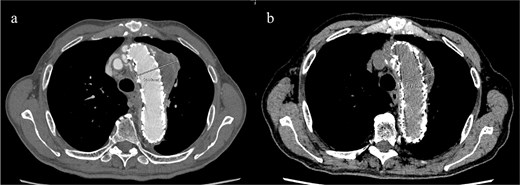

An 83-year-old man presented at our hospital with intermittent hemoptysis. Two years before, he had undergone total arch replacement with FET insertion using a 29 × 120 mm Frozenix J graft (Japan Lifeline, Tokyo, Japan) for a 55 mm aortic arch aneurysm. The Frozenix J graft is a commercially produced open stent graft with an internal skeleton made of nickel-titanium alloy. One year after surgery, postoperative contrast-enhanced computed tomography (CT) showed a reduction in the aneurysm diameter to 49 mm, with no endoleaks (Fig. 1a).

(a) Contrast-enhanced CT 1 year after total arch replacement with FET showing a reduction in aneurysm diameter from 55 mm to 49 mm, with no evidence of endoleak. (b) Contrast-enhanced CT 2 years after total arch replacement with a FET, showing an increase in aneurysm diameter to 56 mm.

CT revealed no endoleak, but the aneurysm had enlarged to a diameter of 56 mm (Fig. 1b). Three-dimensional CT revealed straightening and proximal migration of the FET (Fig. 2). No clear signs of pulmonary parenchymal hemorrhage or findings suggestive of the mass were reported. Laboratory tests indicated mild anemia, with a hemoglobin of 9.7 g/dL and hematocrit of 29.0%. No infectious or inflammatory diseases that could cause hemoptysis were identified.